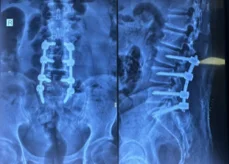

Before & After Clinical Gallery

We showcase real patient cases (with consent), including:

• Pre- and Post-operative MRIs and X-rays

• Disc Herniations, Stenosis, and Spondylolisthesis cases

• Visible improvement in alignment and decompression

After